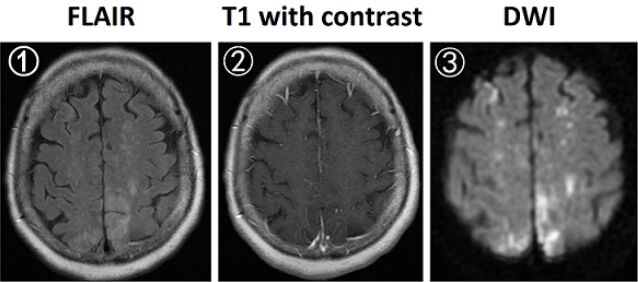

45.70歲女性為肺癌病人,因右腳無力就診,抽血檢查發現D-dimer檢驗數值為16 mg/L(正常值為<0.5 mg/L),腦部磁振造影(MRI)檢查結果如下圖(①fluid–attenuated inversion recovery [FLAIR];② 施打顯影劑之T1影像;③diffusion–weighted imaging [DWI])。下列何者最可能是腦部病灶的原因? (A)多發性腦轉移 (B)肺結核感染 (C)可逆性後腦病變症候群(posterior reversible encephalopathy syndrome, PRES) (D)多發性腦梗塞